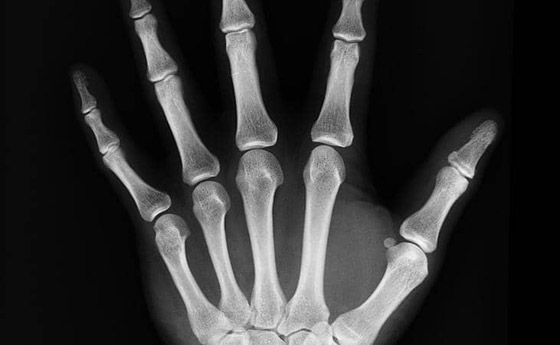

فحص الكثافة: يمكن للأطباء الحصول على صورة أشعة سريعة للتأكد من أن كثافة العظام سليمة. ويساعد هذا الفحص في تحديد مخاطر الإصابة بمرض هشاشة العظام والكسور.